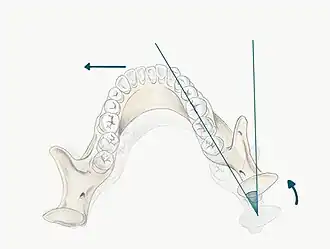

The maxilla forms a crucial aspect of the upper facial skeleton. Two irregularly shaped bones fuse at the intermaxillary suture during development forming the upper jaw. This forms the palate of the oral cavity and also supports the alveolar ridges that hold the upper teeth in place.[3] The lower facial skeleton on the other hand, is formed of the mandible, a U-shaped bone, which supports the lower teeth and also forms part of the TMJ. The mandibular condyle and the squamous portion of the temporal bone, at the base of the cranium articulate with one another.[4]

6) RCP

The patient may be guided into CR using one of the follow methods;

- Bimanual manipulation- manipulating the patient's condyles so they are in CR

- The operator should lightly rest their fingers along the inferior border of the mandible and their thumbs should lie lightly on the anterior aspect of the chin

- When the patient is relaxed place light downward pressure on the chin and light upward pressure under the angle of the mandible

- Deprogramme the jaw by guiding the opening and closing of the jaw and once the patient is relaxed, ask them to close gently and stop when they feel teeth first contacting

- Chin point guidance- one hand is used to apply pressure to the chin guiding the chin posteriorly with some force

In some patients it may be difficult to guide the mandible into CR, for example in those with muscle tension, muscle splinting, occlusal disharmony or parafunctional habit. For these patients a Lucia Jig or deprogramming appliance can be constructed at chair-side.

Mark RCP tooth contacts using articulating paper, note the teeth which are contacting and identify whether this RCP position is causing problems related to the occlusion. For example if there is a heavy contact or interference in RCP this may be the cause of occlusal disturbance. It is important to be able to guide the patient into RCP, as a registration may need to be taken in this position particularly if the occlusion is being reorganised, the OVD is being changed or even just for diagnostic and treatment planning purposes.